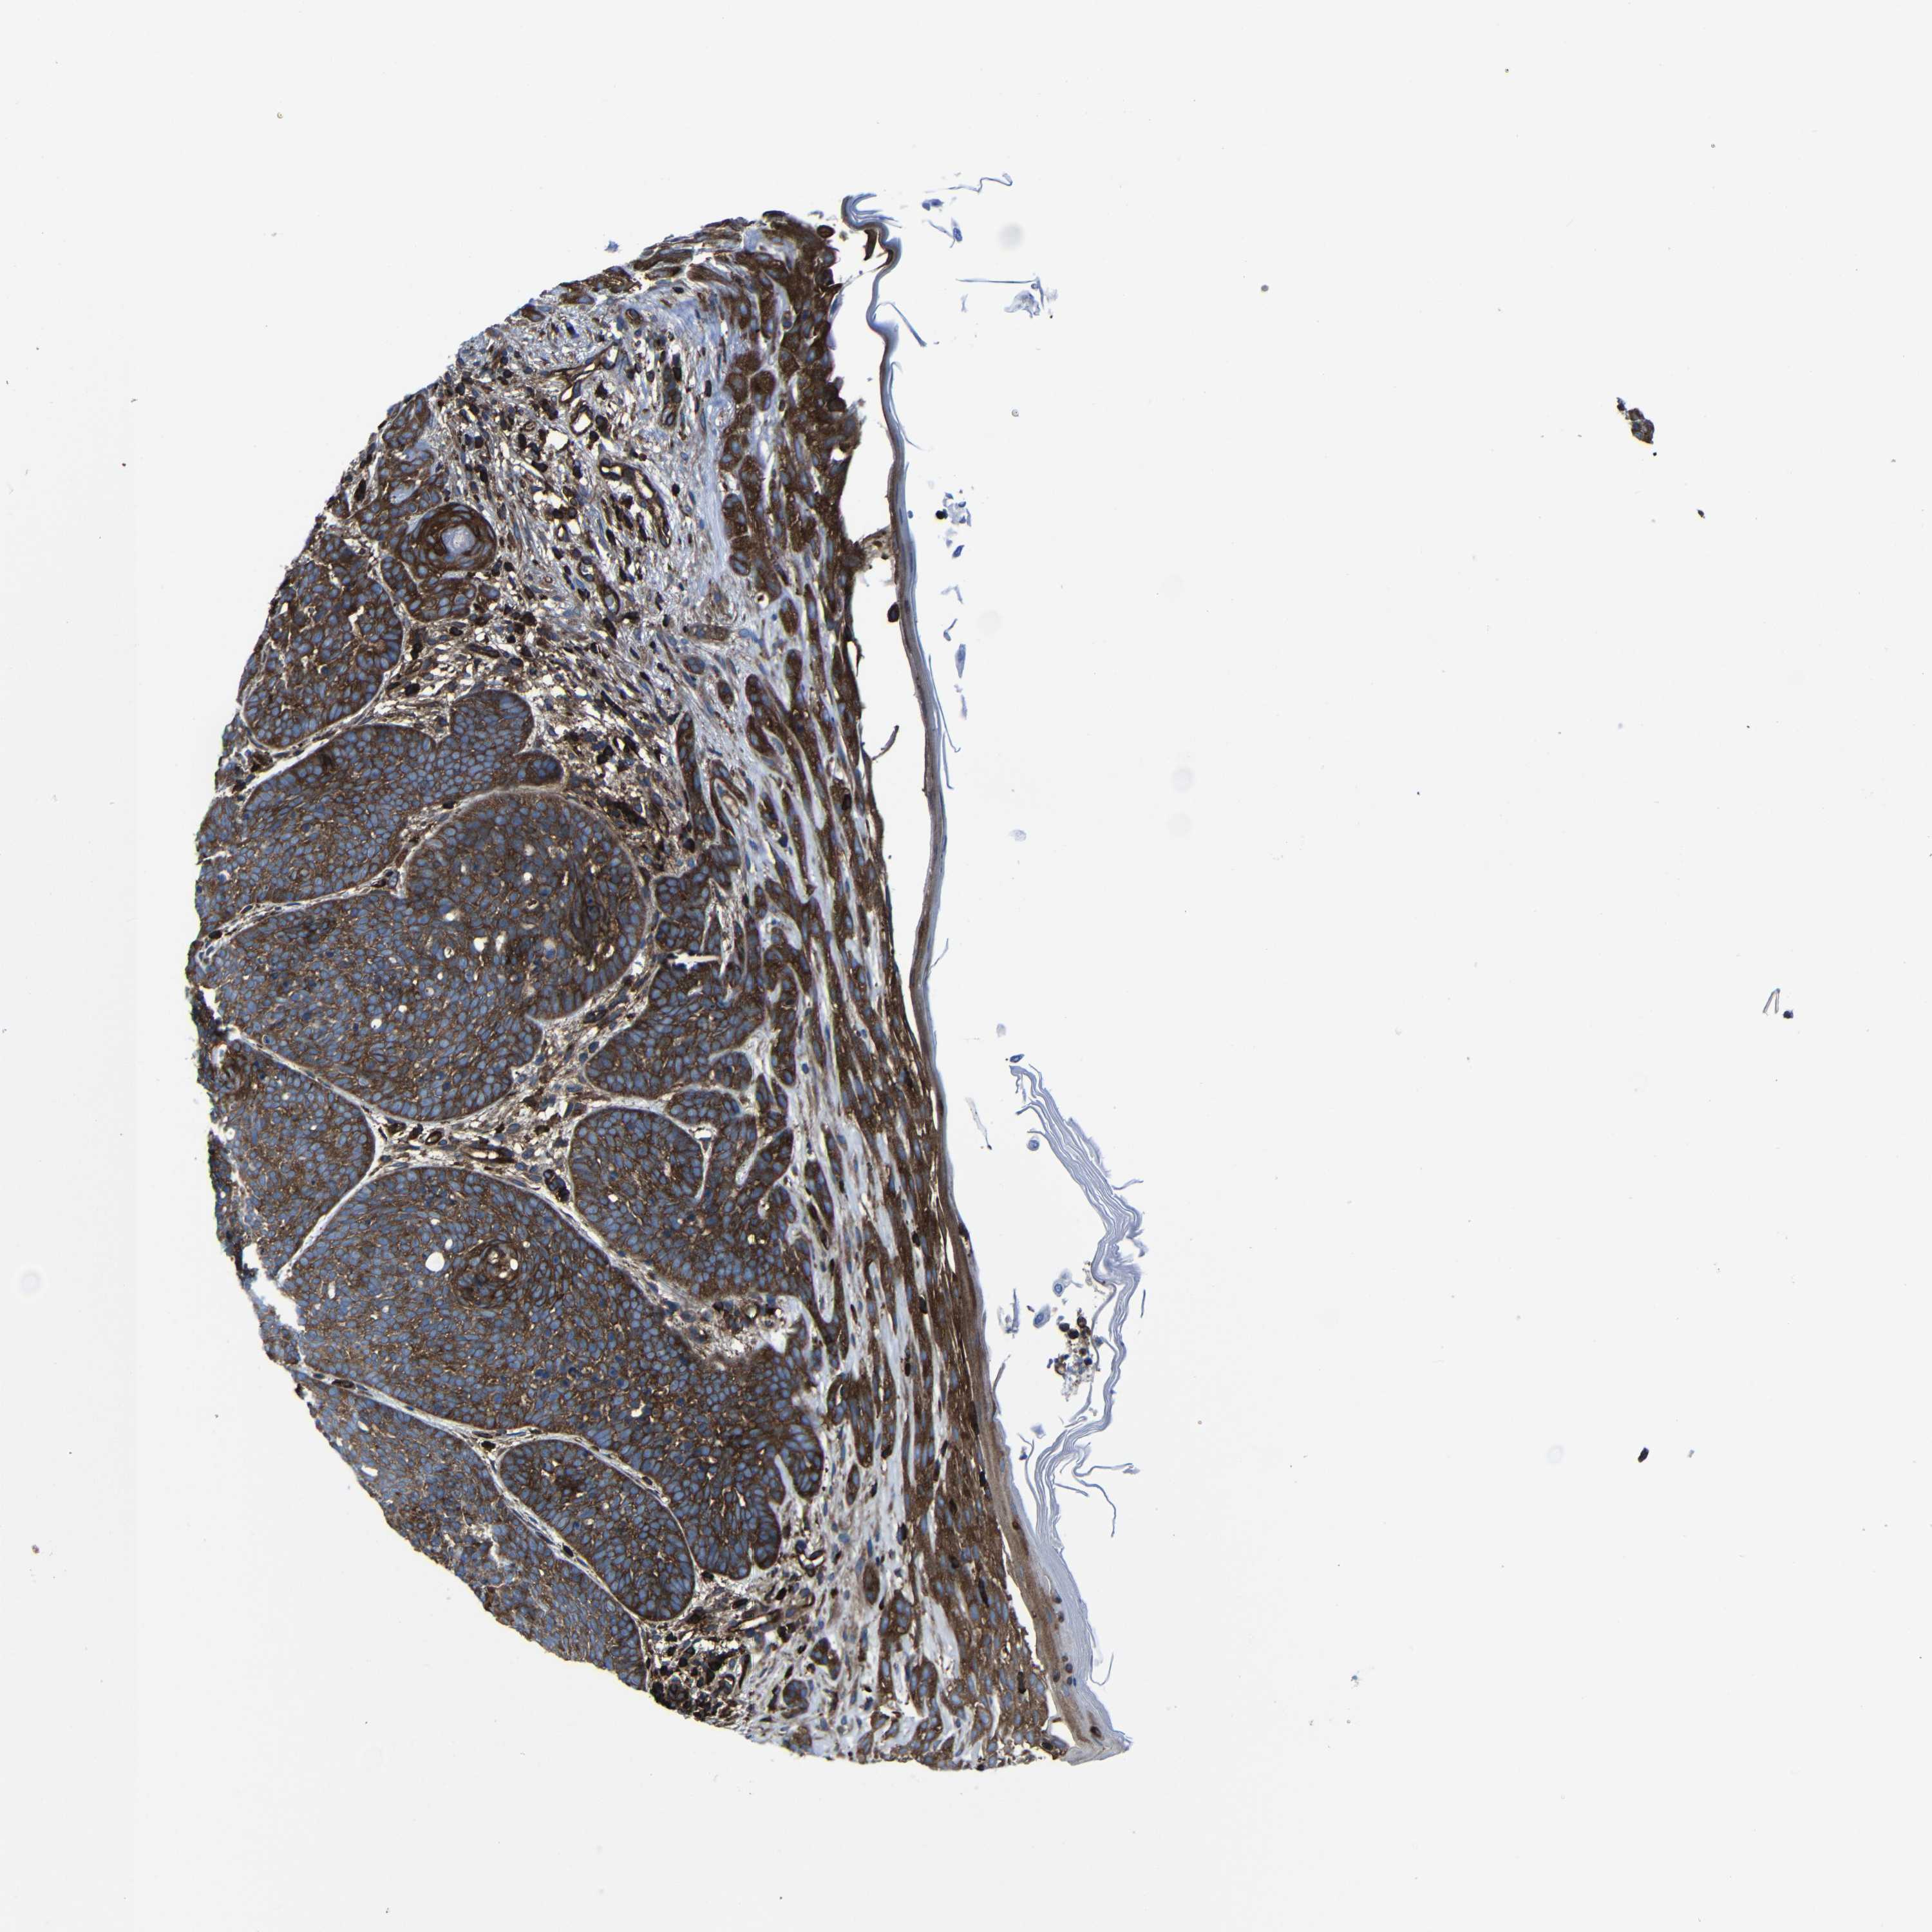

SKIN CANCER - Protein expressioni

A mouse-over function shows sample information and annotation data. Click on an image to view it in a full screen mode. Samples can be filtered based on level of antibody staining by selecting one or several of the following categories: high, medium, low and not detected. The assay and annotation is described here.

Each image is clickable and will lead to virtual microscopy that enables deeper exploration of all samples and also displays staining intensity scores, fraction scores and subcellular localization as well as patient and tissue information for each sample.

Antibody HPA012924

Basal cell carcinoma